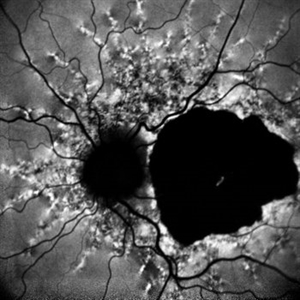

Angioid Streaks Angioid StreaksDec 14 2022 by Pramod Kumar Suman, MBBS, MD Fundus autofluorescence photograph of a 65-year-old male with numerous narrow, irregular streaks radiating in a circumferential pattern within the posterior pole with macular atrophy. Photographer: Pramod Kumar Suman, Retina Foundation, Ahmedabad Imaging device: Mirante Condition/keywords: angioid streaks